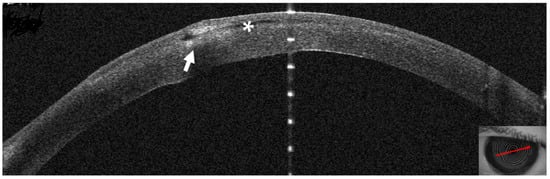

3.1. Patient #1